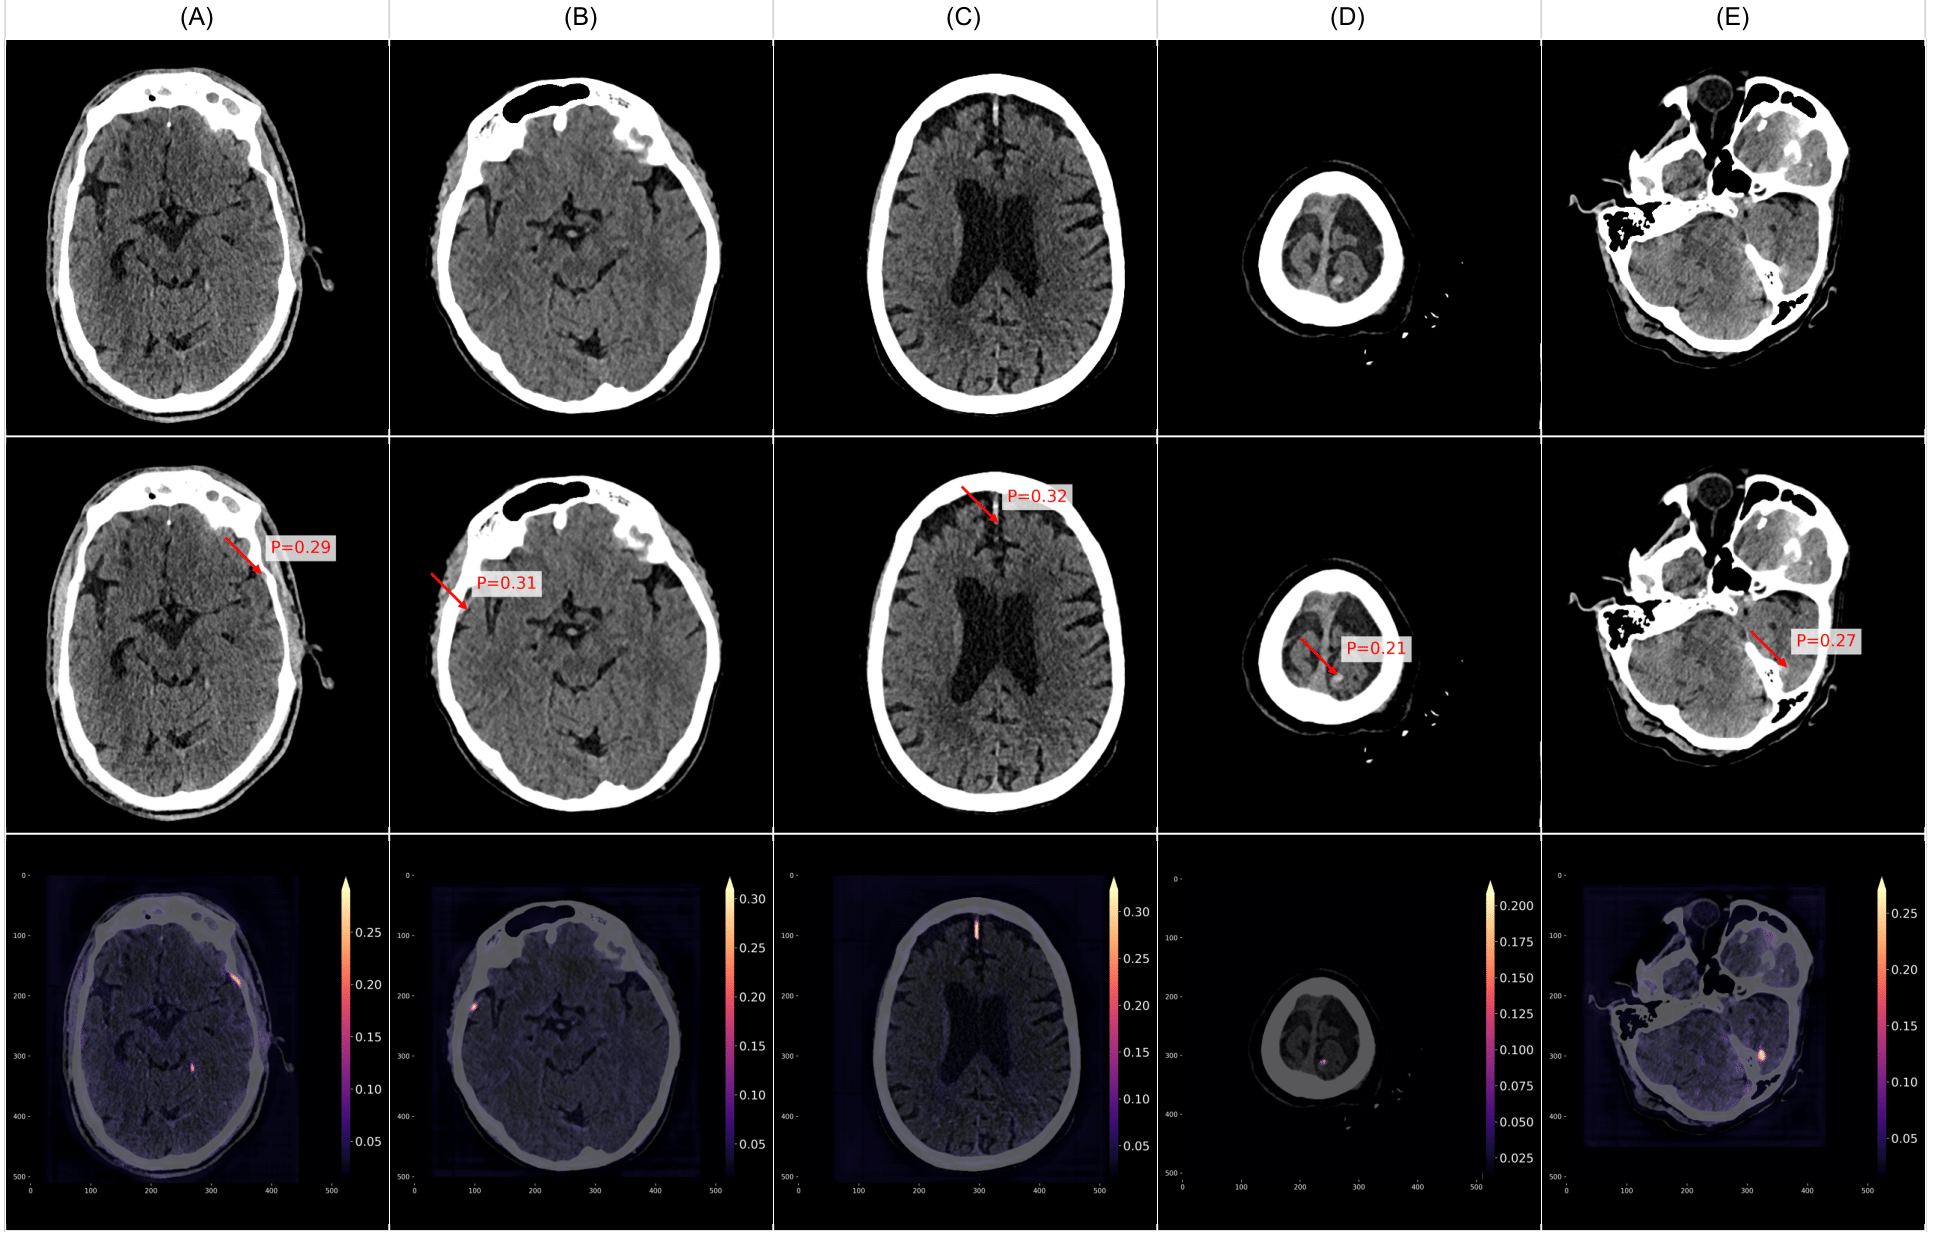

To provide a more intuitive understanding of VIOLA-AI’s performance, we have selected several representative cases for illustration, i.e., True positive case examples (Figure 9), False positive case examples (Figure 10), and False negative case examples (Figure 11).

Figure 11 presents examples of false negative cases, where VIOLA-AI failed to detect intracranial hemorrhage (ICH) in CT scans despite the presence of actual bleeds. Although VIOLA identified regions with potential hemorrhage, the predicted bleed probability values fell below the default detection threshold of 0.5, resulting in their exclusion from positive classifications. These false negatives often involve subtle or small bleeds, lesions in anatomically challenging regions, or bleed types that the model struggles to recognize. Addressing these cases is crucial for enhancing the model’s sensitivity, reducing missed diagnoses, and improving patient safety.